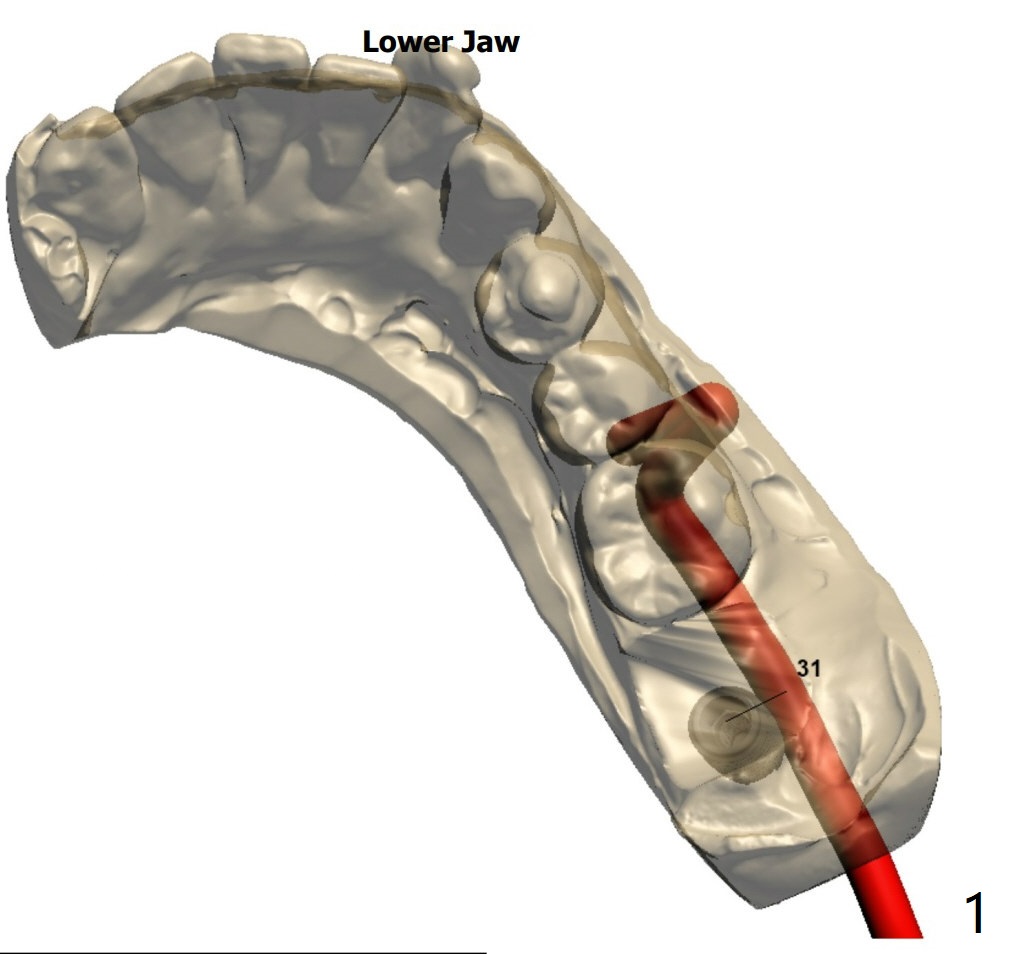

Mesial Slope

A 62-year-old woman

Return to Prevent Molar Periimplantitis (Protocols, Table) Protect Graft Metronidazole 下齿槽神经